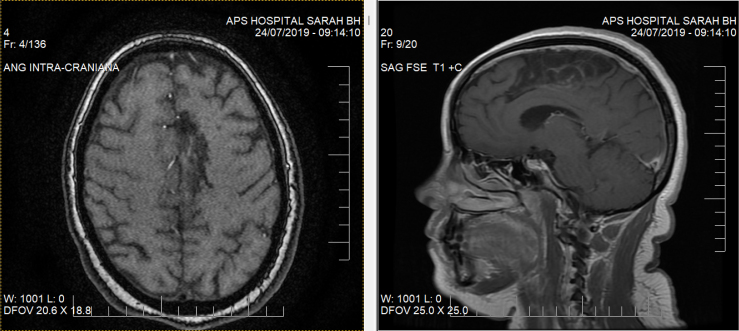

本病例报告了一名妇女在大脑前动脉中风后,左侧辅助运动区受到影响,开始从右向左书写和阅读。文献中没有发现具有完全相同特征的病例。在巴西贝洛奥里藏特市的萨拉康复医院网络(Sarah Network of Rehabilitation Hospitals)接受康复治疗后,她的阅读和书写速度加快了,尽管反转仍在继续。她以适应的方式恢复了以前的活动。会议讨论了这一脑区及其连接的功能障碍会如何干扰阅读策略和方向。

This is the case report of a woman who started to write and read from right to left after anterior cerebral artery stroke, affecting the left supplementary motor area. No cases were found in the literature with exactly the same characteristics. She has been able to read and write faster after rehabilitation approach at Sarah Network of Rehabilitation Hospitals, in the Belo Horizonte city unit, Brazil, despite the maintenance of the inversion. She returned to her previous activities in an adaptive way. It was discussed how the dysfunction in this cerebral area and its connections may disturb the reading strategy and direction.